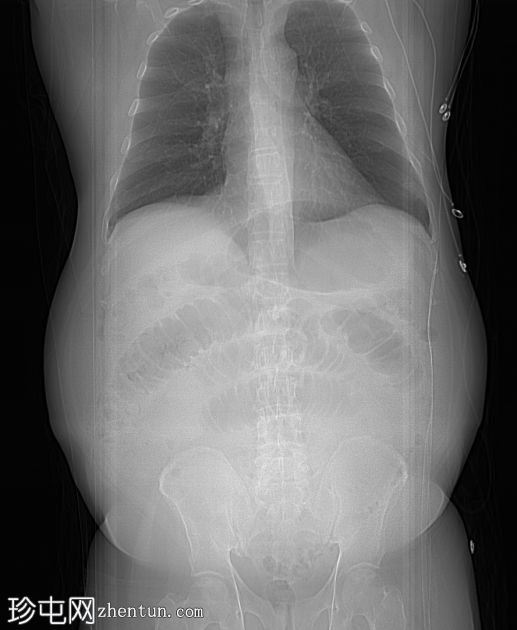

定位片

定位片显示多处扩张的小肠袢。侧位片显示脐部皮下透光区(脐疝)。

多处扩张的小肠袢内可见多个气液平面,直至进入脐疝的肠袢处可见移行点,而从疝口出来的远端小肠袢则呈塌陷状态。

诊断:嵌顿性脐疝继发急性小肠梗阻。